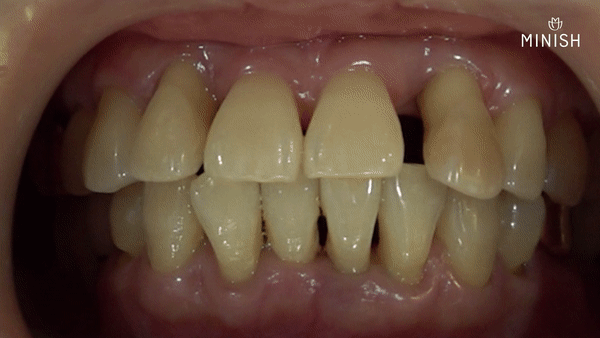

풍치로 인해 잇몸 뼈가 녹고 잇몸이 내려가 치아의 뿌리가 드러나는 경우, 치아는 충분한 지지를 받지 못하고 흔들리게 됩니다.

음식을 자르거나 씹는 기능을 해내지 못하고 이물질만 쌓이는 등 구강에 악영향을 미친다면 발치가 필요할 수 있습니다.

· 질환: 풍치

· 촬영일자: 구강 3.17ㅣ5.27

· 실치료기간: 12일

임플란트 없이도 튼튼한 작은 앞니를 만들어낸 것이죠. 치아를 코팅하는 과정에서 치아의 손상된 형태나 색상, 앞으로 뻗쳐있던 각도까지 개선했습니다. 각 치아의 크기를 재분배해 벌어졌던 공간도 닫을 수 있었습니다.

구강의 건강을 회복하고 아름다운 치아를 넘어 안모의 균형과 건강미가 느껴집니다.